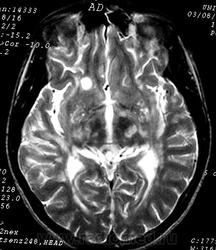

ГМ. Рассеянный склероз 3. +

Рассеянный склероз